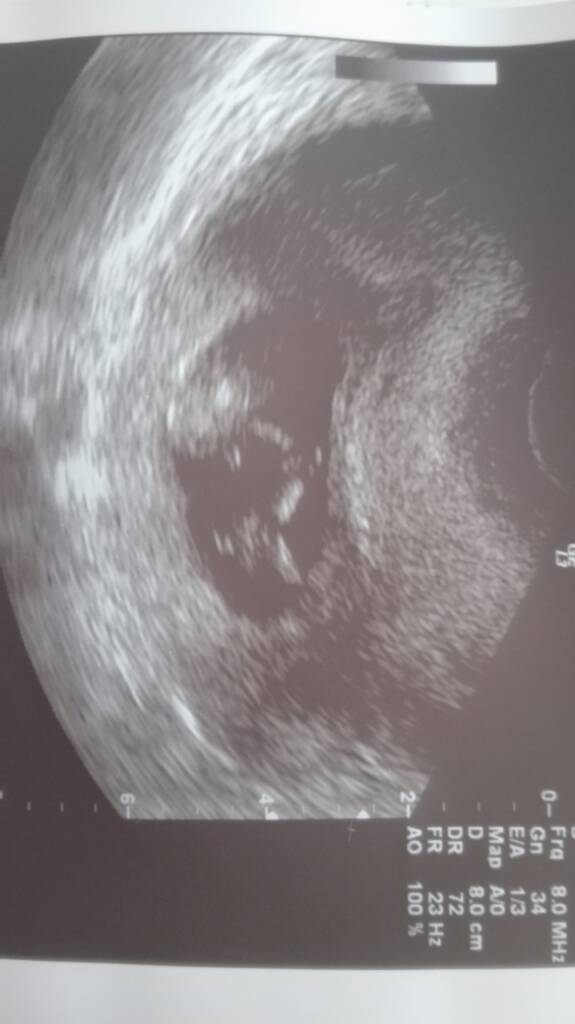

Celem nieinwazyjnego testu prenatalnego HARMONYTM prenatal test jest uspokojenie pary oczekującej dziecka, że nie występują u niego najczęstsze trisomie chromosomów.

HARMONYTM prenatal test polega na badaniu krwi kobiety ciężarnej. Badany jest DNA płodu, którego małe ilości są obecne w krwioobiegu matki.

HARMONYTM prenatal test wykrywa ponad 99% przypadków trisomii chromosomów pary 21 oraz wysoki odsetek przypadków trisomii 13 oraz 18. Pozwala także na określenie płci płodu.